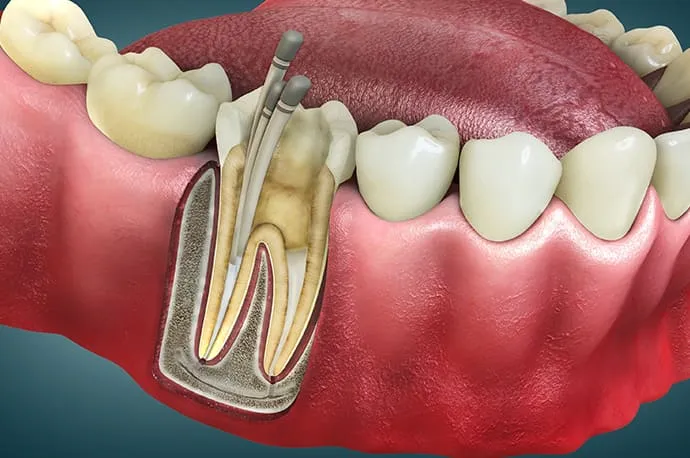

①根管拡大

ニッケルチタンロータリーファイルを使用し、根管を適切な形に広げながら、内部に存在する細菌を物理的に取り除いていきます。

根管の長さの測定

根管口が見つかったら、ファイルと呼ばれる細い針金のような器具を根の先まで挿入し、根管の正確な長さを測定します。この工程が、治療の精度を左右する重要なポイントになります。

根管の清掃・消毒

測定した長さに合わせて、柔軟性のあるニッケルチタンファイルで根管を最小限に広げます。同時に消毒剤を使用し、根管内部を徹底的に洗浄・消毒していきます。